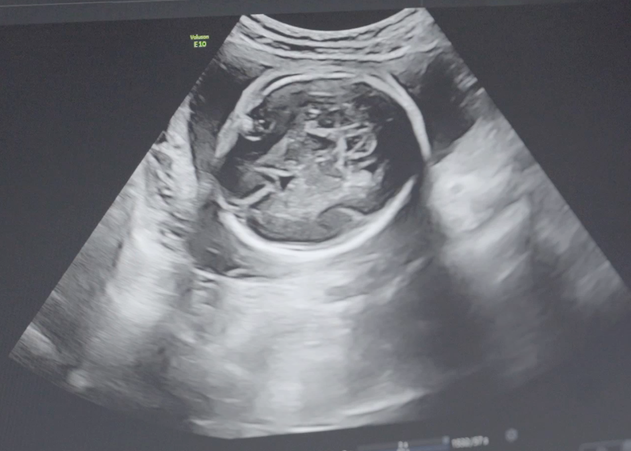

B超是利用超声波的回波来获取图像,通过图像处理技术,医生可以观察到人体内部的结构和器官,从而进行诊断和鉴定。B超检查对男女鉴定也有一定的作用,主要通过观察胎儿的性别特征来判断其性别。

虽然B超技术在医学上有着广泛的应用,但在男女鉴定中的准确率却有一定的局限性。首先,胎儿的性别在早期发育阶段并不明显,容易造成误判。其次,B超图像的解读和诊断有一定的主观性,不同医生的经验和专业水平也会对结果产生影响。此外,胎儿的体位和姿势等因素也可能影响B超图像的质量,从而影响准确性。

然而,尽管存在以上局限性,B超在男女鉴定中的准确率仍然比较高。研究表明,当胎儿达到12周以上时,B超技术的准确率可以达到90%以上。在20周以上,准确率更高,接近100%。因此,在实际应用中,B超仍然是一种较为可靠的男女鉴定方法。